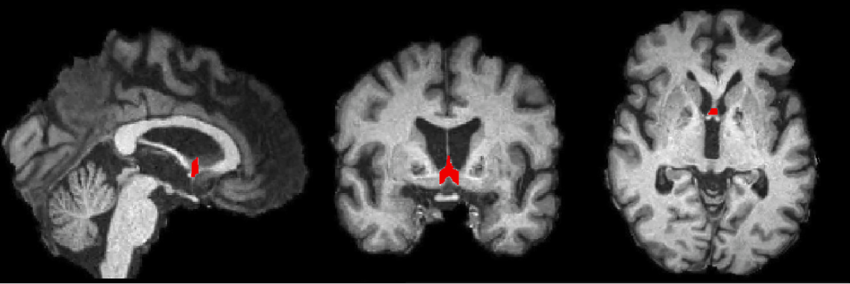

What do H.M.’s brain scans show

A loss of volume in the temporal lobe, where the hippocampus is found

What structure is this

septal nuclei

What structure is this

fornix